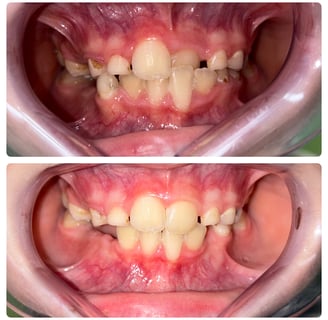

Aparatele dentare mobile sunt utilizate in tratamentul anomaliilor dento-maxilare, forme usoare sau moderate. Se numesc mobile pentru ca sunt purtate doar pe timpul noptii, plus cateva ore ziua.

Varsta ideala pentru inceperea tratamentului este la 6-7 ani ( dentitia mixta),copiii fiind in crestere, iar maxilarele destul de maleabile pentru a raspunde bine la tratament.

Cu ajutorul acestora putem corecta pozitia dintilor, muscatura, largi arcadele, imbunatatind aspectul zambetului si functia.